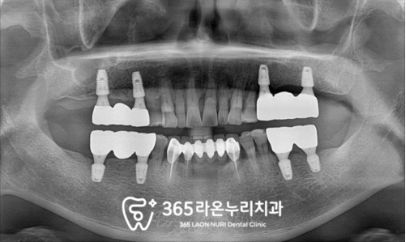

▮ 6. 최종 보철 수복

모든 진료가 끝난 모습을 보겠습니다.

전체적으로 적응 기간이 필요했기에

여러 번 제작과 조정을 거친 후

환자가 편안함을 느끼실 때까지

맞춰드리느라 시간은 좀 더 걸렸던 것 같네요.

그러나 보이는 것처럼

위아래 심미-저작 기능을 모두 회복하고

충분히 편안함을 느끼셨을 때

최종 보철을 올려드리는 게 맞다 생각했기에

환자와 충분히 기간을 조율하며

마무리해드렸습니다.